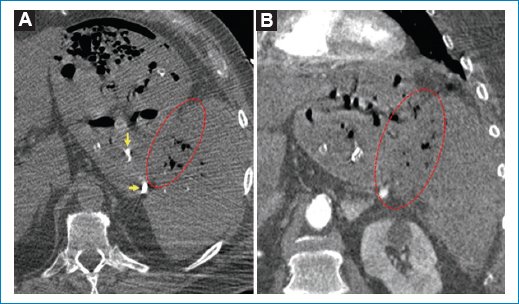

Al mejorar los parámetros hemodinámicos se realizó tomografía computada (TC) de abdomen, observando pérdida de los planos de separación entre la curvatura mayor del estómago y el bazo, con evidencia de continuidad del contenido gástrico al espacio periesplénico y en el interior del bazo, no pudiendo delimitar planos de clivaje con el estómago, así como material de embolización en la cavidad gástrica, interpretando este hallazgo como una FGE sin lesión proliferativa visible al momento del estudio (Fig. 2). El paciente intercurre con taquicardia, acidosis y mal manejo del medio interno ocho horas después de la realización del estudio, por lo que el servicio de cirugía general realiza laparotomía exploradora con gastrectomía parcial y esplenectomía.

Figura 2. TC axial (A) y coronal (B) posterior a la estabilización del paciente. Se observa la pérdida de planos de separación entre el estómago y el bazo, con imágenes similares al contenido gástrico en los tejidos periesplénicos y el bazo (círculo rojo punteado). Se constata material de embolización en la cavidad gástrica (flechas amarillas).